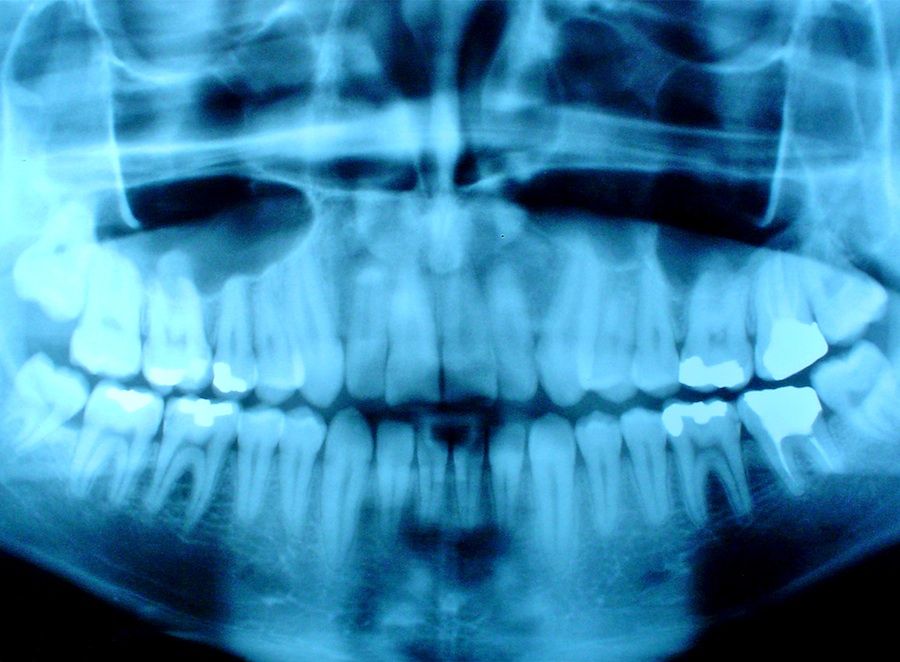

- Имплантология – начальное планирование имплантации до 3D КЛКТ снимка, контроль за приживлением имплантов и костного графта после выполнения синус-лифтинга.

- Ортопедическая стоматология – в качестве диагностики состояния зубов и их корней перед планированием любого вида протезирования зубов и протезирования имплантов.

- Ортопед, используя снимок, определяет готовность челюстей к протезированию, подбирает типы имплантов и протезов, контролирует приживаемость имплантов.

- В хирургической стоматологии – появляется возможность оценить патологический очаг, планировать и контролировать постановку имплантов.

Снимок позволяет:

-

изучить объем и плотность костной ткани;

оценить состояние корней соседних зубов, их расположение;

выбрать нужные по размеру и форме импланты.